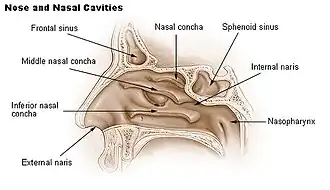

Nasopharynx

The upper portion of the pharynx, the nasopharynx, extends from the base of the skull to the upper surface of the soft palate.[2] It includes the space between the internal nares and the soft palate and lies above the oral cavity. The adenoids, also known as the pharyngeal tonsils, are lymphoid tissue structures located in the posterior wall of the nasopharynx. Waldeyer's tonsillar ring is an annular arrangement of lymphoid tissue in both the nasopharynx and oropharynx. The nasopharynx is lined by respiratory epithelium that is pseudostratified, columnar, and ciliated.

Polyps or mucus can obstruct the nasopharynx, as can congestion due to an upper respiratory infection. The auditory tube, which connects the middle ear to the pharynx, opens into the nasopharynx at the pharyngeal opening of the auditory tube. The opening and closing of the auditory tubes serves to equalize the barometric pressure in the middle ear with that of the ambient atmosphere.

The anterior aspect of the nasopharynx communicates through the choanae with the nasal cavities. On its lateral wall is the pharyngeal opening of the auditory tube, somewhat triangular in shape and bounded behind by a firm prominence, the torus tubarius or cushion, caused by the medial end of the cartilage of the tube that elevates the mucous membrane. Two folds arise from the cartilaginous opening:

- the salpingopharyngeal fold, a vertical fold of mucous membrane extending from the inferior part of the torus and containing the salpingopharyngeus muscle.

- the salpingopalatine fold, a smaller fold, in front of the salpingopharyngeal fold, extending from the superior part of the torus to the palate and containing the salpingopalatine muscle.[3] The tensor veli palatini and levator veli palatini are lateral to the fold and do not contribute.

Nose and nasal

Nose and nasal -